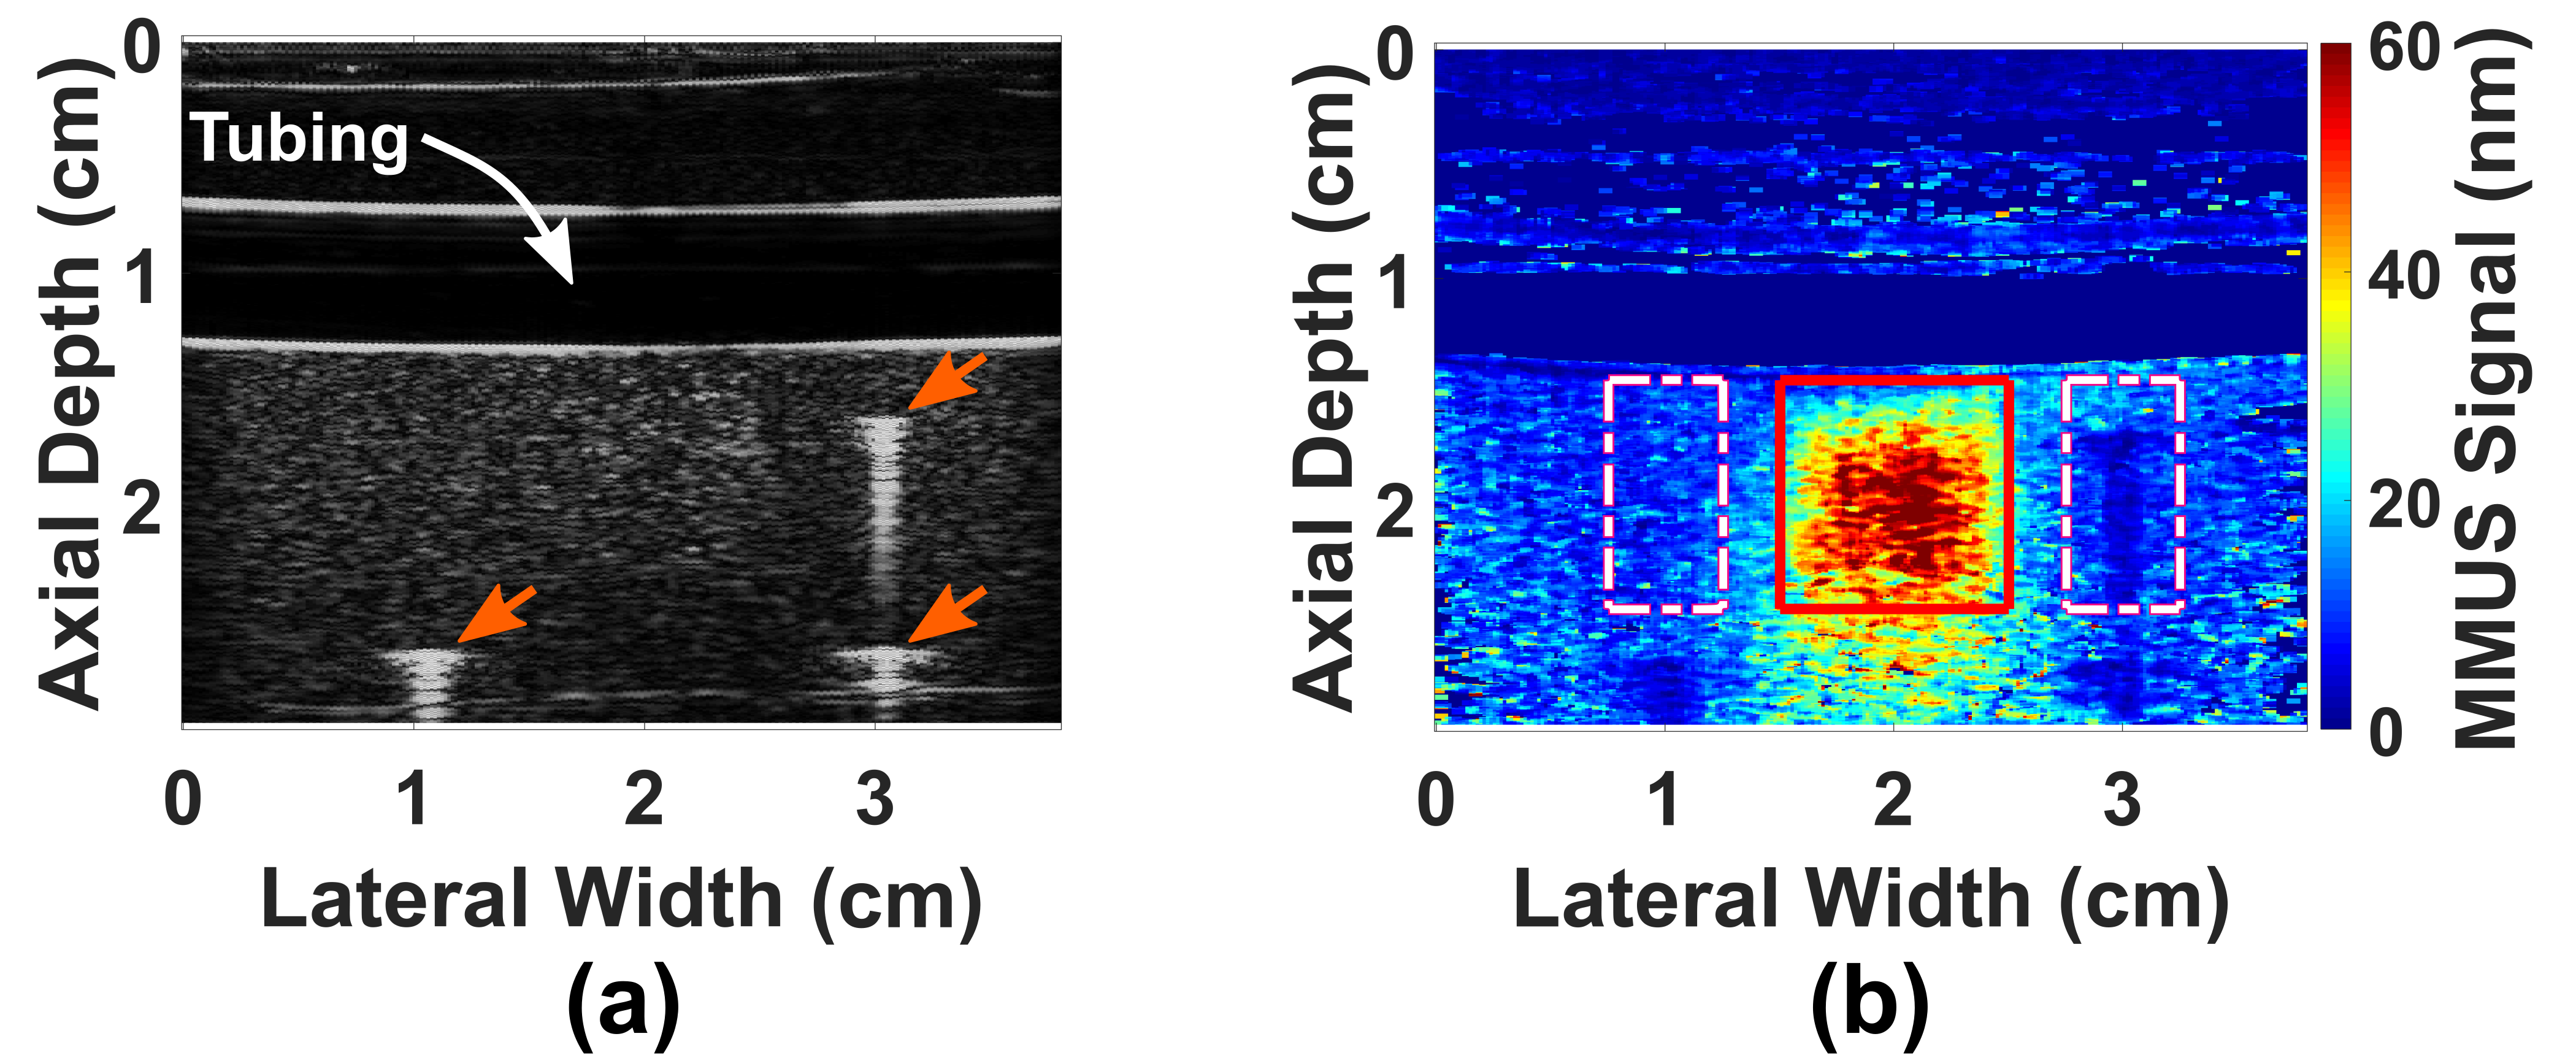

Past experiments in our lab have already shown that this method of imaging using SPIO-labeled platelets as contrast agents is possible. Oldenburg et al, 2010 showed that Optical Coherence Tomography (OCT) – an imaging method analogous to Ultrasound, but using optics rather than acoustics – showed that SPIO-platelets specifically adhered to a thrombus formed on a damaged vascular endothelium and provided contrast, compared to no contrast from that on un-damaged endothelium. Importantly, we have recently demonstrated that MMUS can sense simulated thrombus in the presence of pulsative flow (Levy et al, 2018). An MMUS image of such a model SPIO-labelled clot beneath a model thin plastic artery is shown in Figure 2.

Fig. 2. A thin plastic tube embedded in gelatin models a blood vessel passing through human tissue. Water pumps though the tube (simulating blood flow), and a cubical gelatin model thrombus containing iron oxide particles is placed below the vessel. Figure (a) shows what is seen with conventional ("B-mode") ultrasound, and figure (b) shows what is seen with MMUS. The model thrombus is only visible in the MMUS image, and it appears as a red and yellow square beneath the tube. The true location of the model thrombus (shown by the thin red outline) can be seen to align well with the detected location. More on these images may be found in our recent publication: (Levy et al, 2018).